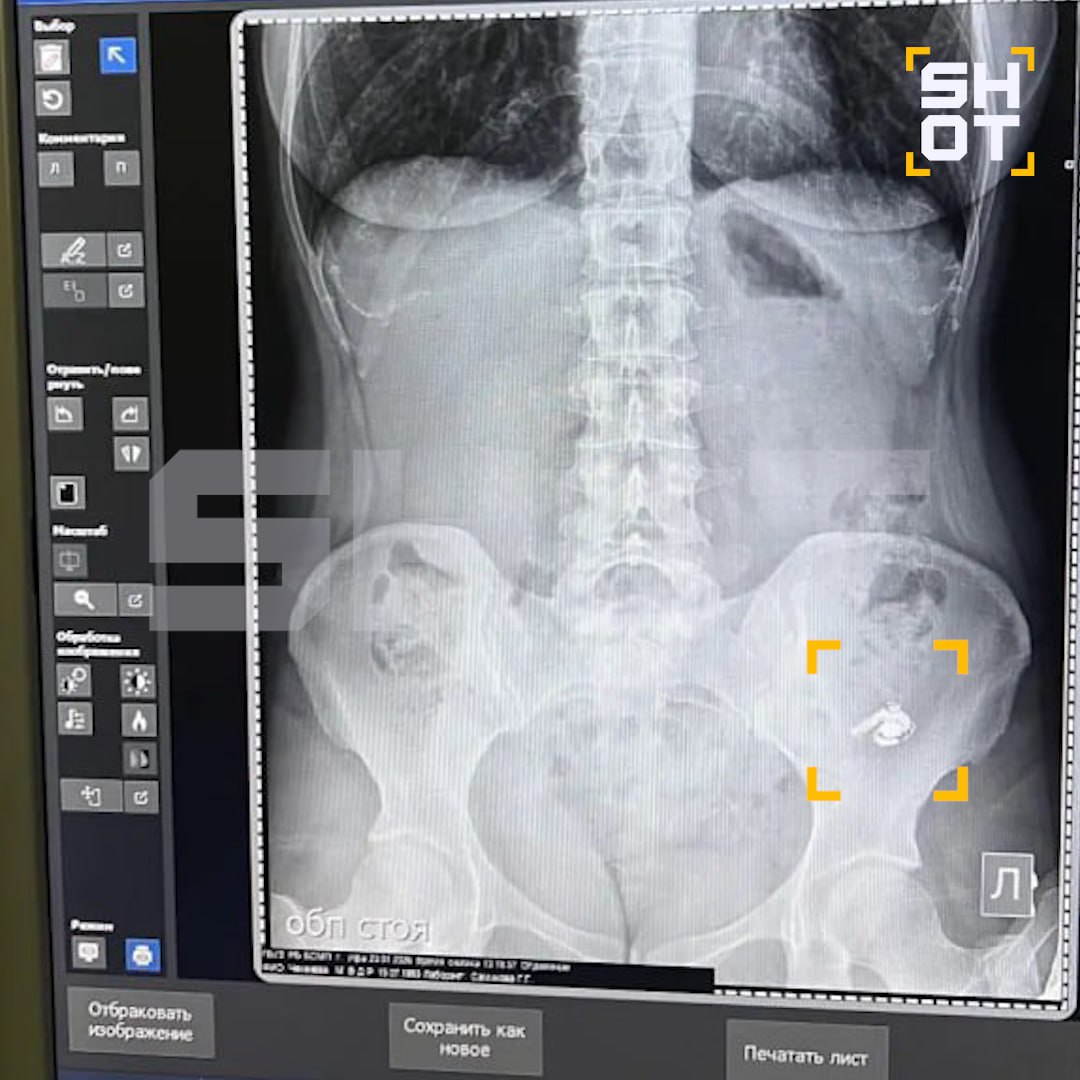

Позже она полезла в карман за наушниками и обнаружила, что одного из них нет. После этого девушка обратилась в больницу. Рентген подтвердил, что AirPod находится внутри организма.